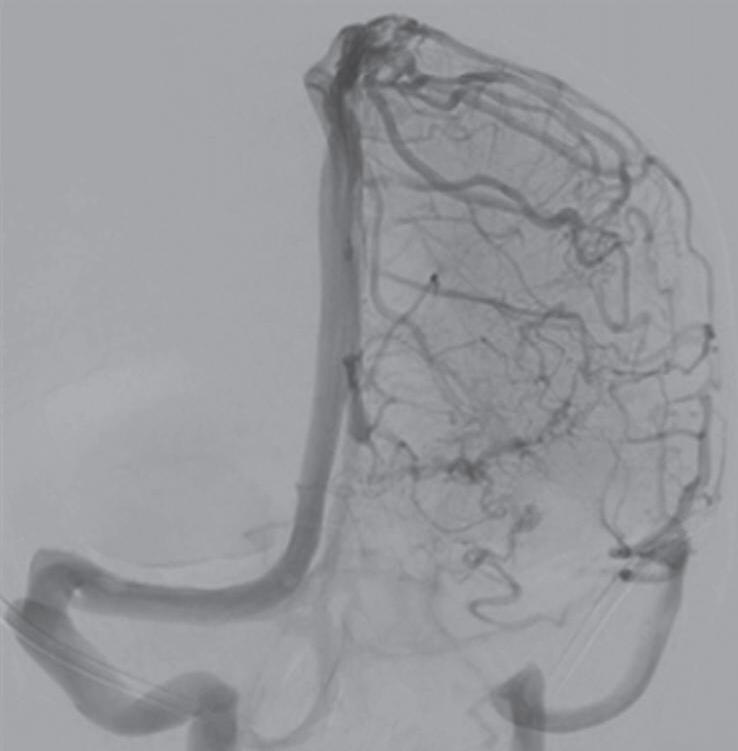

Com relação ao fluxo no interior do nidus, alguns autores classificam-nas em alto fluxo (Fig. 1-8) e baixo fluxo (Fig. 1-9). São consideradas de alto fluxo aquelas em que a opacificação após injeção de contraste ocorre apenas na malformação, em contrapartida, nas de baixo fluxo, ocorre opacificação da MAV e de outras artérias normais do mesmo território vascular. Exemplificando as lesões de alto fluxo temos as malformações arteriais, as malformações arteriovenosas e as fístulas arteriovenosas, enquanto as lesões de baixo fluxo são representadas pelas malformações venosas, linfáticas e capilares.25

Fig. 1-8. (a-c) RNM T1 com contraste, cortes sagital (a), coronal (b) e axial (c) demonstrando MAV não rota com nidus localizado no lobo occipital à esquerda (setas longas). (d) Arteriografia digital cerebral com injeção de contraste via carótida direita (AP) mostrando a contribuição da carótida direita na irrigação da MAV contralateral. (e,f) Com injeção de contraste via carótida esquerda, em Perfil e AP respectivamente, observa-se nidus compacto nutrido por ramos da artéria cerebral média à esquerda e a veia de drenagem precoce se dirigindo para o seio sagital superior. Projeções em AP (g) e em perfil (h) demonstrando a contribuição do sistema vertebrobasilar por meio de ramos distais da artéria cerebral posterior à esquerda e drenagem para os seios sagital superior e sigmoide à esquerda (setas curtas).